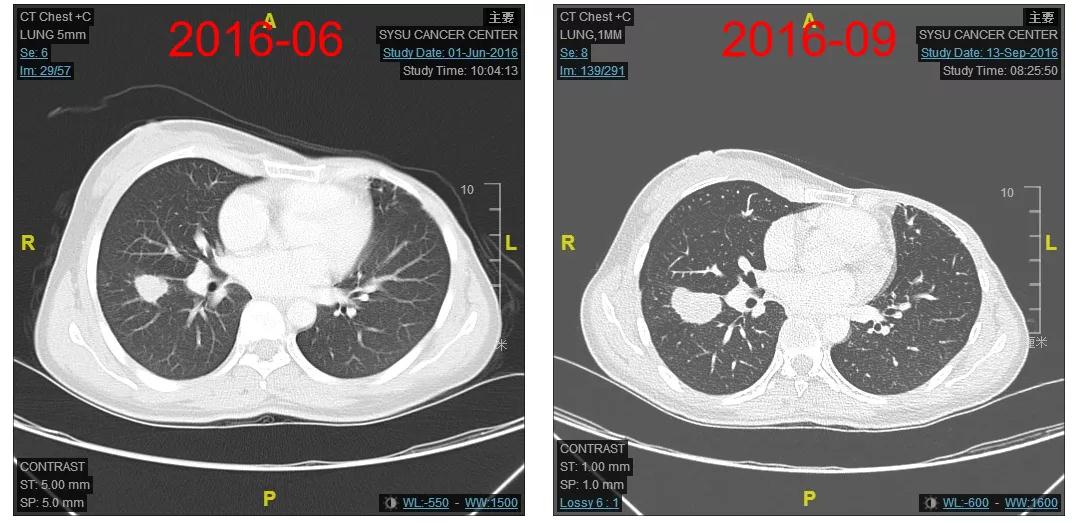

2016-12-06开始使用T-DM1(恩美曲妥珠单抗)方案治疗,首次疗效评估PR,后续最佳疗效CR(图2-3)。

图2

图3

患者为初诊IIIC期的HER2阳性乳腺癌,单靶曲妥珠单抗辅助治疗过程中发生多发肺转移;治疗采用T-DM1治疗获得迅速缓解(CR),PFS已近5年;用药过程中主要毒性集中在肝酶升高、血小板下降及中性粒细胞下降,均为1-2度,可对症处理或自行缓解;T-DM1一线治疗方案耐受性好,生活质量无影响。

当前病例报告中的患者为初诊ⅢC期HER2阳性乳腺癌,在单靶曲妥珠单抗辅助治疗过程中发生多处肺转移,参加MO28231临床试验,采用T-DM1一线治疗获得迅速缓解,目前已获得近5年的PFS,且患者耐受性良好,用药过程中的肝酶升高、血小板下降及中性粒细胞下降均为1-2度,可对症治疗或自行缓解。该病例的诊治经验提示,对于经过抗HER2(新)辅助治疗进展的患者,T-DM1是高效、安全的一线治疗选择。